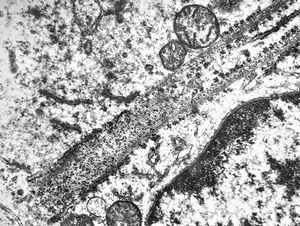

M,26y. | ribosome-lamella bodies in adenocarcinoma

M,41y. | ribosome-lamella complex in tricholeukocyte -hairy cell leukemia, spleen